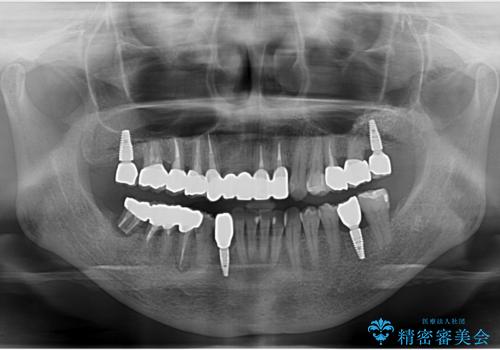

- 全体的な虫歯治療、根管治療、および歯周病治療を行いました。

歯周病治療につきましては歯周ポケット除去のために歯周外科処置(APF)を行っています。

左下6の欠損については左下7はワイヤー部分矯正でアップライトを行い、補綴スペースを確保しています。

右下犬歯は歯周病の進行が重度のため、やむなく抜歯をし、骨増生後にインプラント埋入を行っています。

根管治療は横浜桜木町歯科 大元先生が担当しました。

右下7の根管治療および再植は銀座院 林先生が担当しています。(抜歯は希望されなかったため、再植を行い、現在経過観察中です。)